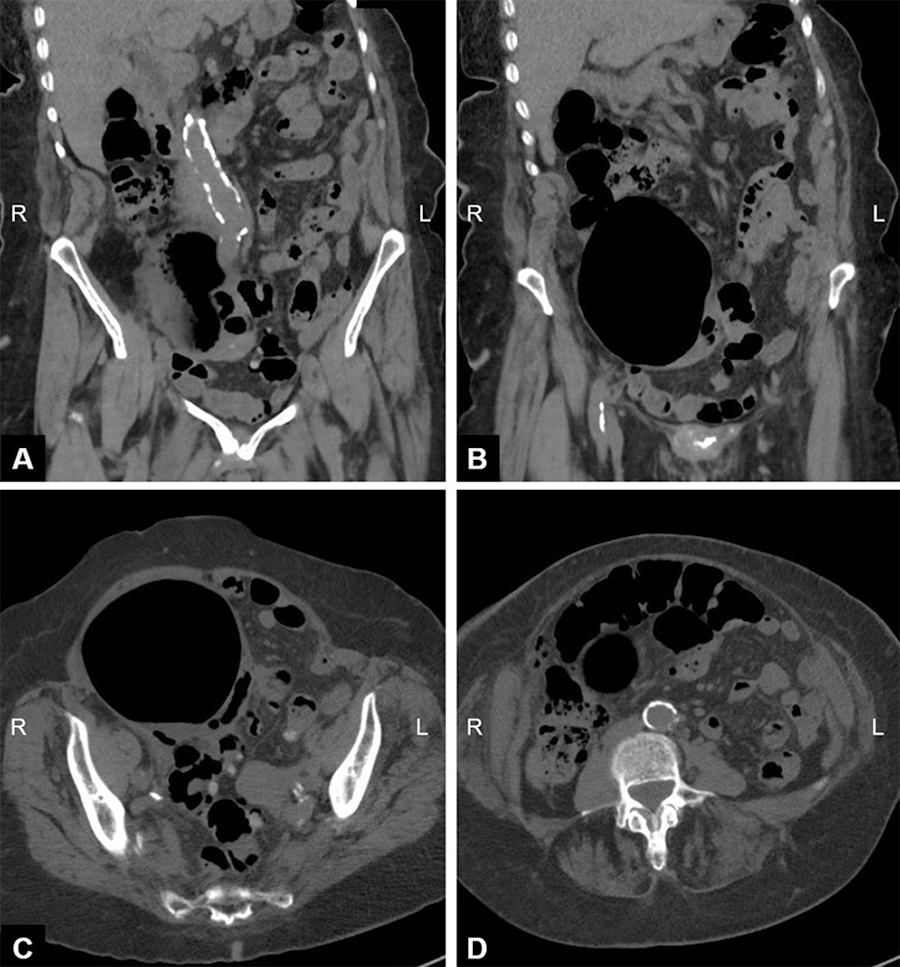

The patient tolerated the procedure well with no postoperative complications and was discharged eight days later to a skilled nursing facility. The pathology report confirmed that the cystic mass was a tubo-ovarian abscess likely secondary to sigmoid diverticulitis, as demonstrated by foreign plant material and multinucleated giant cells within the abscess wall (Figure 2). The patient underwent a barium enema one month later, which showed acceptable filling of the colon (Figure 3). An ileostomy reversal was completed, and the patient has been doing well postoperatively.

Figure 3. Postoperative Barium Enema Showing Diverticula but Adequate Filling of Colon with Right Anterior Oblique A) and Anterior-Posterior (B) Views. Published with Permission